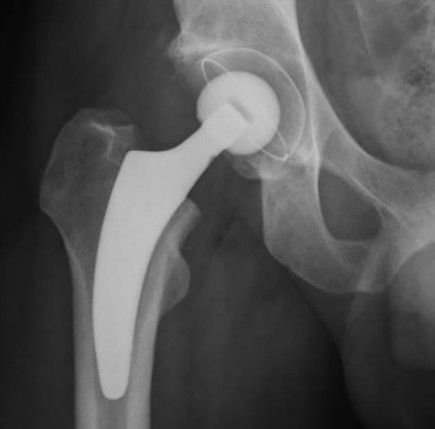

K pooperačnímu sledování pacienta je využíváno pobytu na monitorovaném lůžku buď přímo v rámci ortopedického oddělení, nebo eventuálně pak na pracovištích JIP (jednotka intenzivní péče) či ARO (anesteziologické a resuscitační oddělení). Již v této fázi může být dle zvyku pracoviště zahájena vertikalizace pacienta. V rámci pooperačního období je zcela zásadní dodržovat opatření, která jsou shrnuta v tabulce 1. Těmito zásadami je nutno se řídit po dobu minimálně šesti týdnů od operace. Stav po úspěšné implantaci TEP kyčle ukazuje obrázek 4.

Obr. 4 Správná pozice komponent TEP kyčelního kloubu

TEP – totální endoprotéza

Zdroj: Ortopedická klinika FZS UJEP a MNUL.